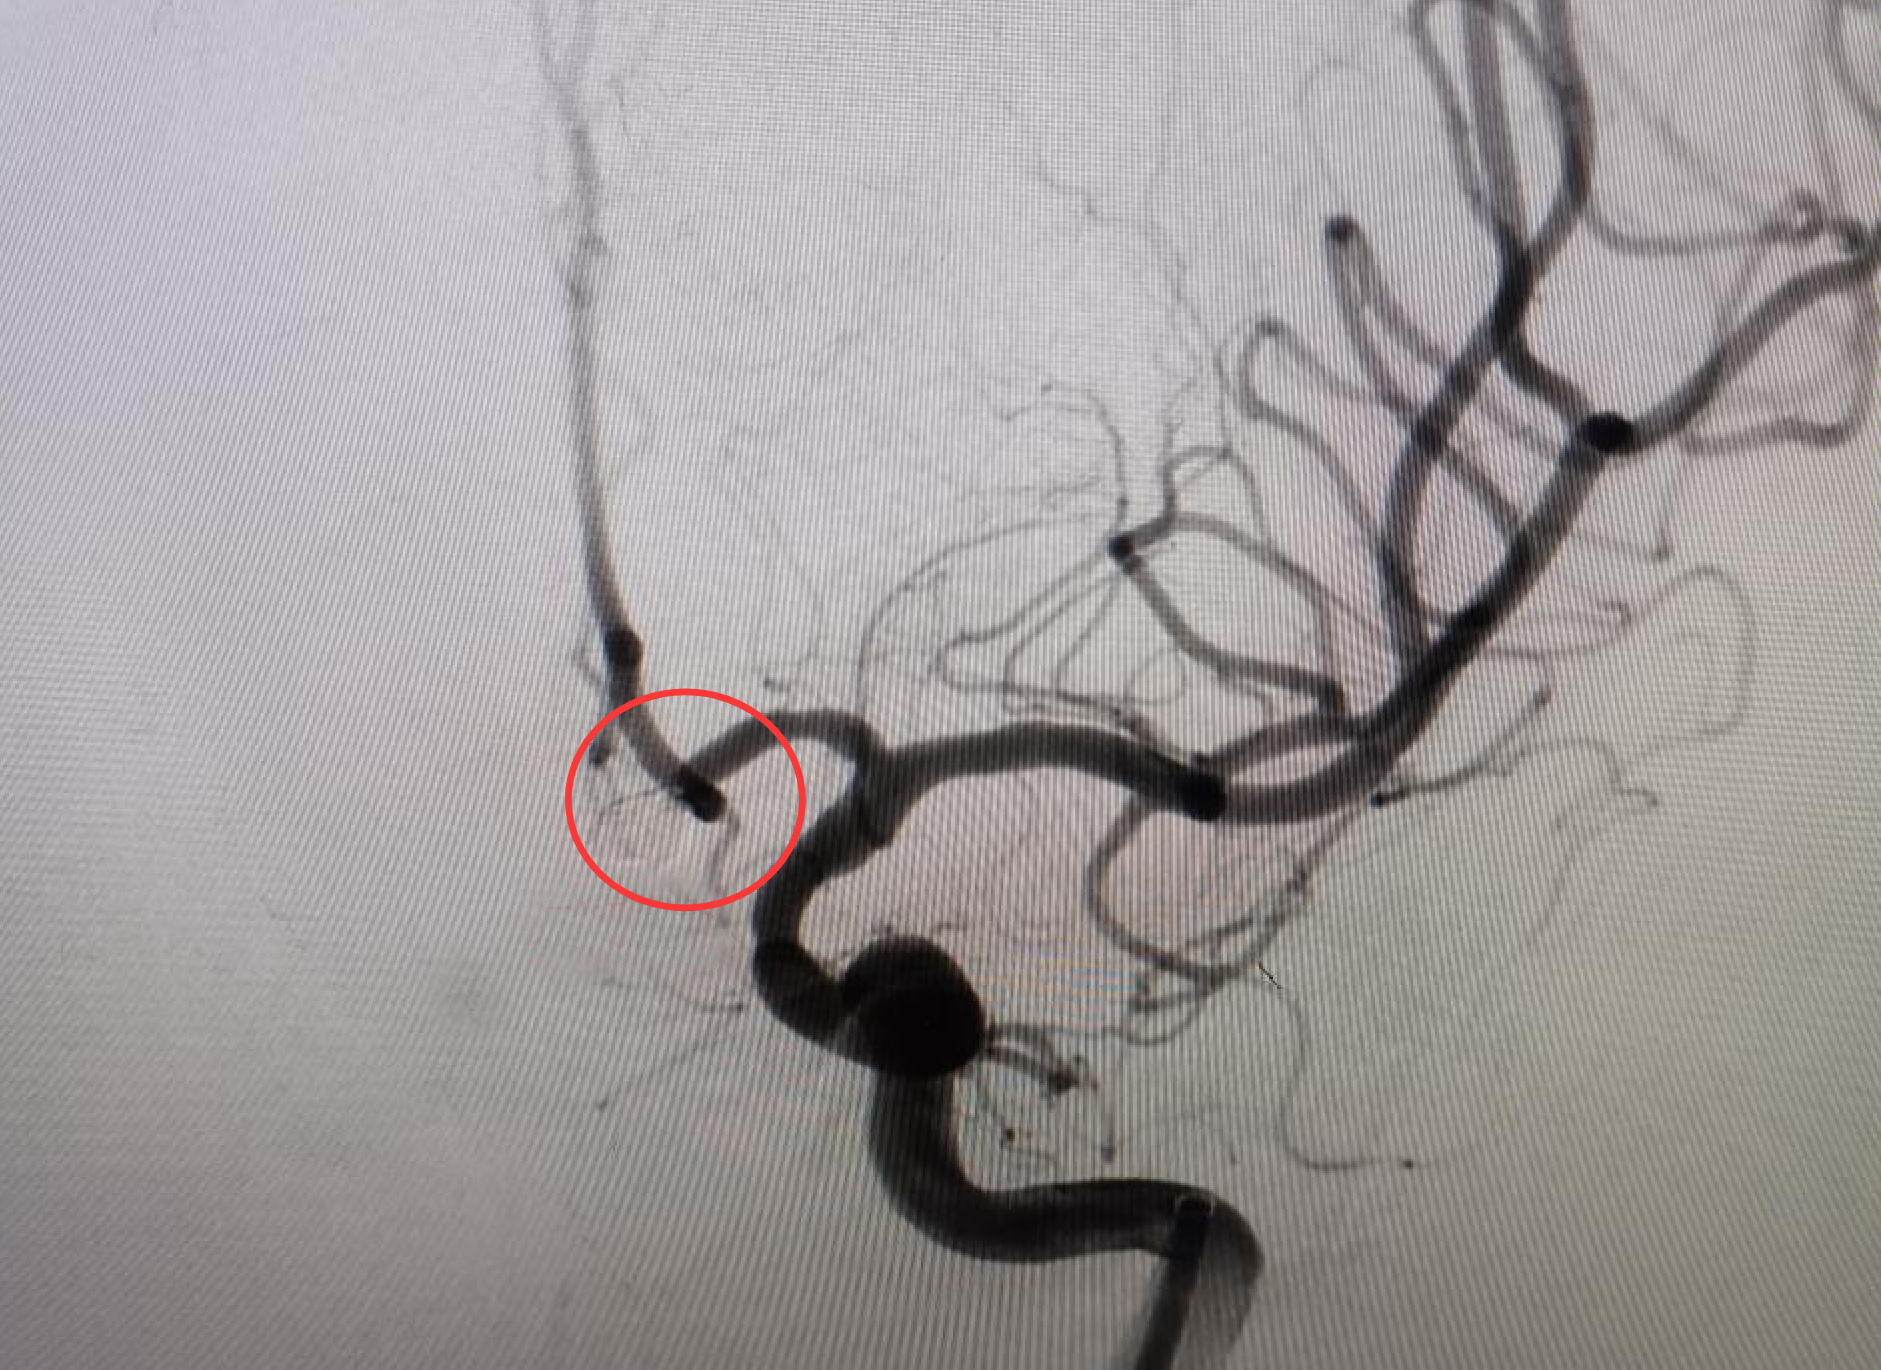

急诊医生发现他双侧瞳孔缩小,对光反射减弱。鉴于病情十分危急,医生立即启动绿色通道,在10分钟内完成了头颅CT,结果显示其蛛网膜下腔广泛出血,这是颅内动脉瘤破裂的典型表现。随后的颅脑CTA 显示,盘林的前交通动脉上有一个5毫米的不规则“泡泡”。据了解,脑动脉瘤并不是真的瘤,只是动脉血管壁鼓起的一个“小泡泡”。这种“小泡泡”被称为颅内“不定时炸弹”,一旦破裂(即脑出血),如果抢救不及时,分分钟就有可能殒命。

在造影机投射的血管 “地图” 上,神经外科副主任医师陈日朝操控着直径 0.56 毫米的微导管,从患者股动脉穿刺点出发,沿着髂动脉、颈动脉的蜿蜒路径上行。在 0.1 毫米级的血管成像实时更新下,微导管进入体内约1米左右,抵达动脉瘤腔。手术团队默契配合,将 5 枚弹簧圈填入其中完成致密栓塞。手术很成功,从确诊到完成“拆弹”仅用2小时17分钟。手术全程微创,患者大腿根部仅留 2 毫米穿刺痕迹。

为什么塞满了弹簧圈就能化险为夷呢?据介绍,神经介入技术在动脉瘤中的运用,是用一个微导管进入动脉瘤体内,从微导管里输送一种特殊的合金材料,叫弹簧圈,它比头发丝都细,非常柔软,它在动脉瘤内部像缠毛线圈一样,最终形成一个网篮状的结构,这样弹簧圈填塞动脉瘤之后,会把动脉瘤从内部给闭塞掉,血流就不会流入动脉瘤,这样动脉瘤就不会破裂或破裂的可能性非常小了。